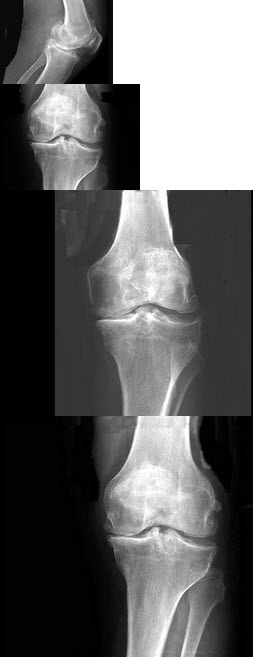

B.大弯

C.胃角

D.胃窦

E.十二指肠球部

点击查看答案

B.第四肋骨前缘下缘水平线

C.第四肋骨下缘的最低点

D.第四肋骨前端下缘的最低点

E.第四肋骨前端下缘的最低点水平线